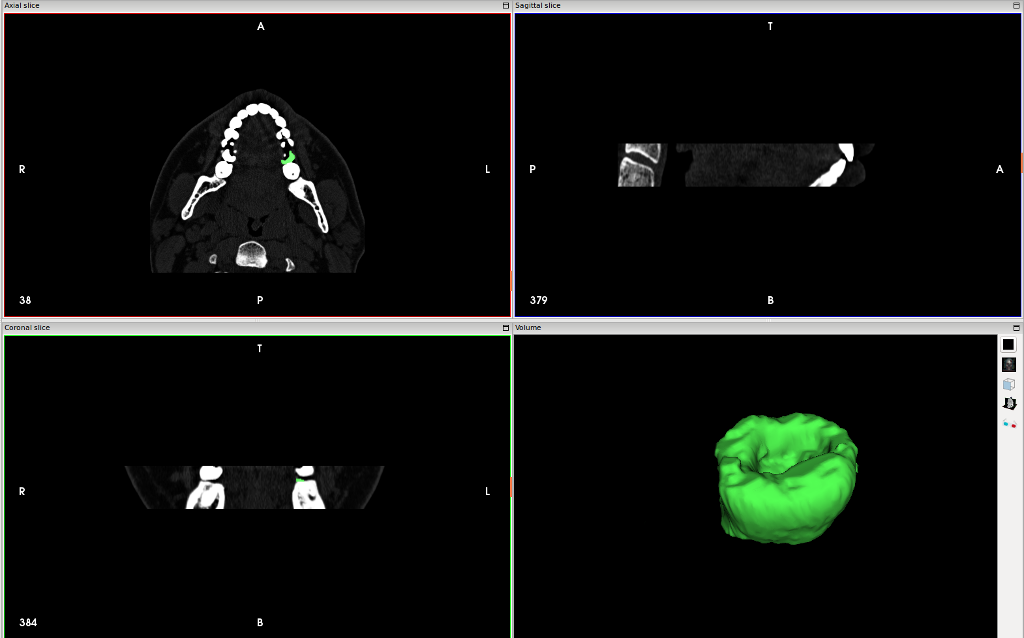

Немного про формат данных: DICOM — стандартизованный формат обмена медицинской информацией и метаинформацией. На выходе из компьютерного томографа это самое стандартное что есть! Как раз в этом формате попросил записать результаты КТ на диск.

Программа InVesalius — для реконструкции 3D из DICOM снимков. Достаточно простая в использовании и не столь многофункциональна как 3D slicer. Но зато быстро позволяет добиться результата. Так я получил 3D модель лицевой части, повращал свой череп во вьюпорте и воскликнул «бедный Йорик!».

3D slicer намного более функциональный пакет чем InVesalius. 3D slicer для ученых-медиков, как Blender для 3D графики. Функциональный, но надо потратить время на изучение. У меня нет столько свободного времени и желания углубляться в этот софт. Лучше я продолжу писать статьи про аспектно-ориентированное программирование, а эти программы оставлю студентам-медикам и ученым. Для меня стало неожиданностью что столько медицинских программ есть в open source!!!

Ручной процесс сегментирование изображения 36 зуба на КТ в InVesalius очень напоминает процесс создания маски кистью в растровом редакторе.

Автоматическое сегментирование изображения захватывало все костные ткани в изображениях и поэтому не подошло. Если интересно чтобы записал скринкаст процесса создания модели, пишите в комментариях.

В завершении этой фотосессии, сделал 3D модель коронковой части 36 зуба после сегментации вручную срезов томографии.

После лечения зуба за свой счет- это тот же объем что и на фото выше. Интерфейс InVesalius

Интересно, удавалось ли другим пациентам в такой ситуации доказать реальную степень разрушения зуба. Делает ли какая-либо клиника такую экспертизу? Теоретически, модель зуба может быть объективным аргументом в споре со страховой. По-моему отличная тема для диссертации стоматолога!!!